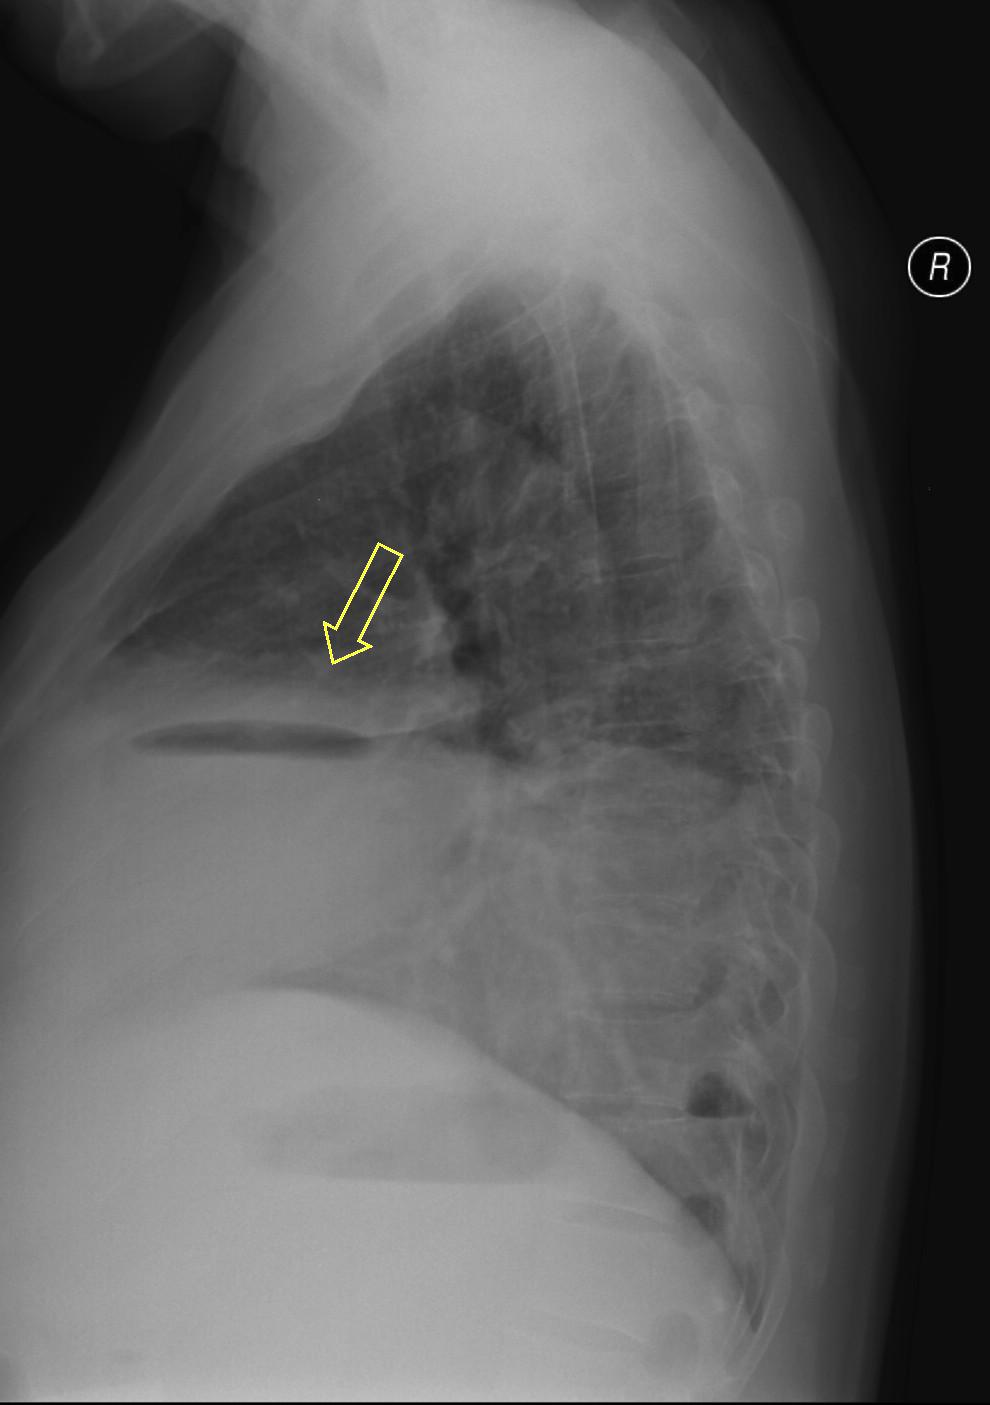

19. Tuberculosis, bidirectional chest radiographs and HRCT. (coronal reconstruction)

75 year old man: hx of hypertension, smoking. Symptoms: dyspnea, productive cough. Moist rales of auscultatory findings above the LLL, tension irritability in the level of lower dorsal spine.

a.) Chest radiograph, bilateral: Mild increased vascular markings. Extensive patchy lobar infiltration in the RUL Previous TB specific lesions in the left apex. The diaphragm contour is blurry on the right side (appr. 4 finger-wide pleural effusion). Cardiomegaly. Medium large dilated sclerotic aorta.

b.) HRCT: Reticular pattern of 10x10x5 cm area in the right apex (1st segment), (septal thickenings), mosaic-like ground glass opacity in the righ apex. Subpleural total atelectasis (mainly 1st segment): irregular mainly nodular soft tissue streak associated with the pleura (max. appr. 1 cm thickness). Some tiny subpleural emphysematous bullae in the right apex.